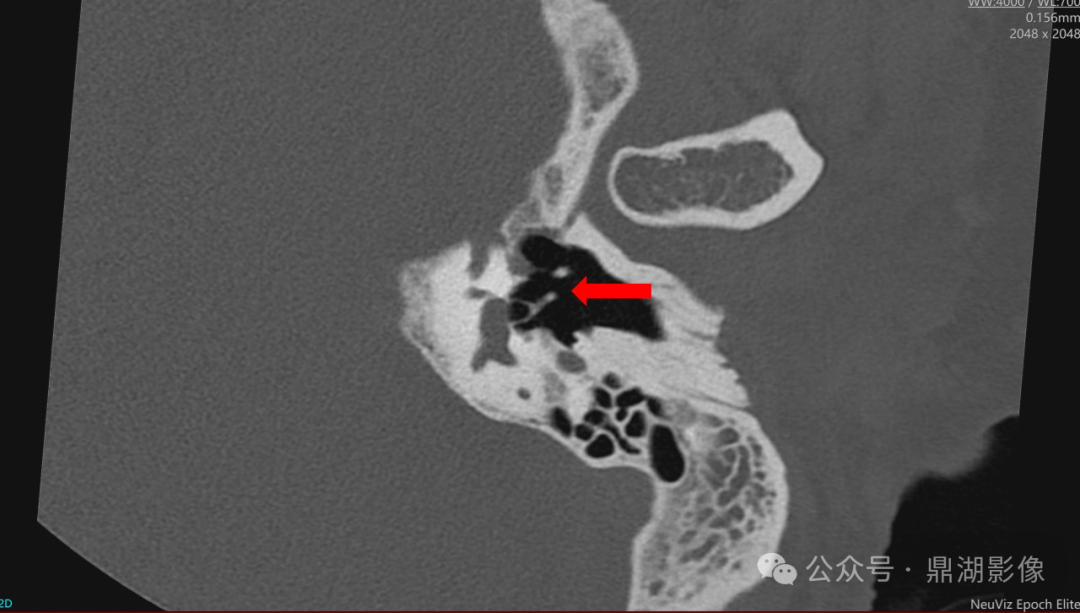

图 内耳高分辨率扫描显示:听小骨(镫骨)结构

NeuViz Epoch Elite通过46.5lp/cm超高空间分辨率可精准评估镫骨形态及毗邻关系,为耳科手术(如镫骨切除术)提供关键解剖信息。